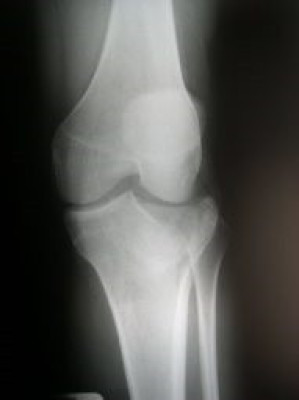

Fractura de plato tibial reducida bajo control artroscópico

Envíado por Dr. Luis Rodolfo Morales Choto